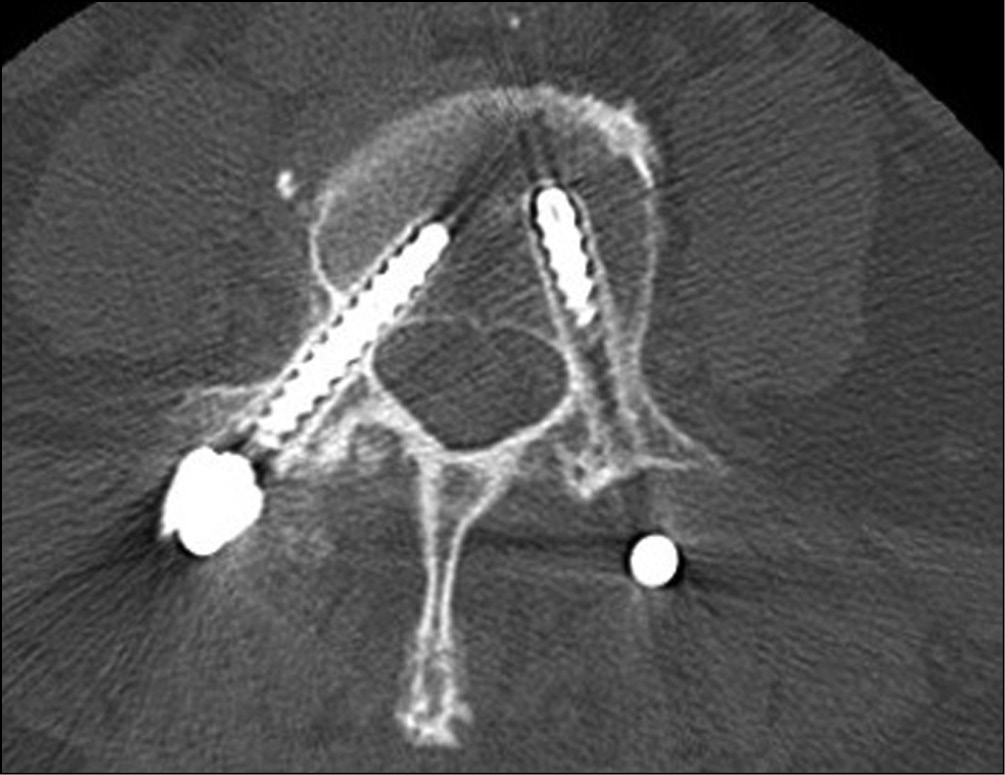

В 1-й группе несформированный костный блок встречается чаще, чем во 2-й группе (22,6 % против 20,7 % соответственно), хотя различия и не значимы (p > 0,05) (табл. 3). У 6 пациентов 1-й группы определена резорбция не только вокруг винтов, но и вокруг межтелового импланта (рис. 3). При этом во всех случаях также определялось проседание кейджа.

Рис. 3. Резорбция вокруг винтов и межтелового импланта, проседание межтелового импланта через 7 мес. после первичного хирургического вмешательства